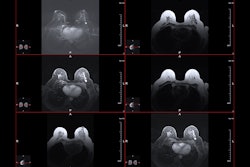

The researchers investigated the frequency of insurance denials for annual breast MRIs in women with this genetic variant and reviewed exam denial trends via a study that included data from 682 women with BRCA1/2 germline mutations who had screening breast MRIs ordered between 2020 to 2021 at a high-risk breast cancer clinic. The team tracked whether the exams were performed and assessed rates of exam denials and disease outcomes.